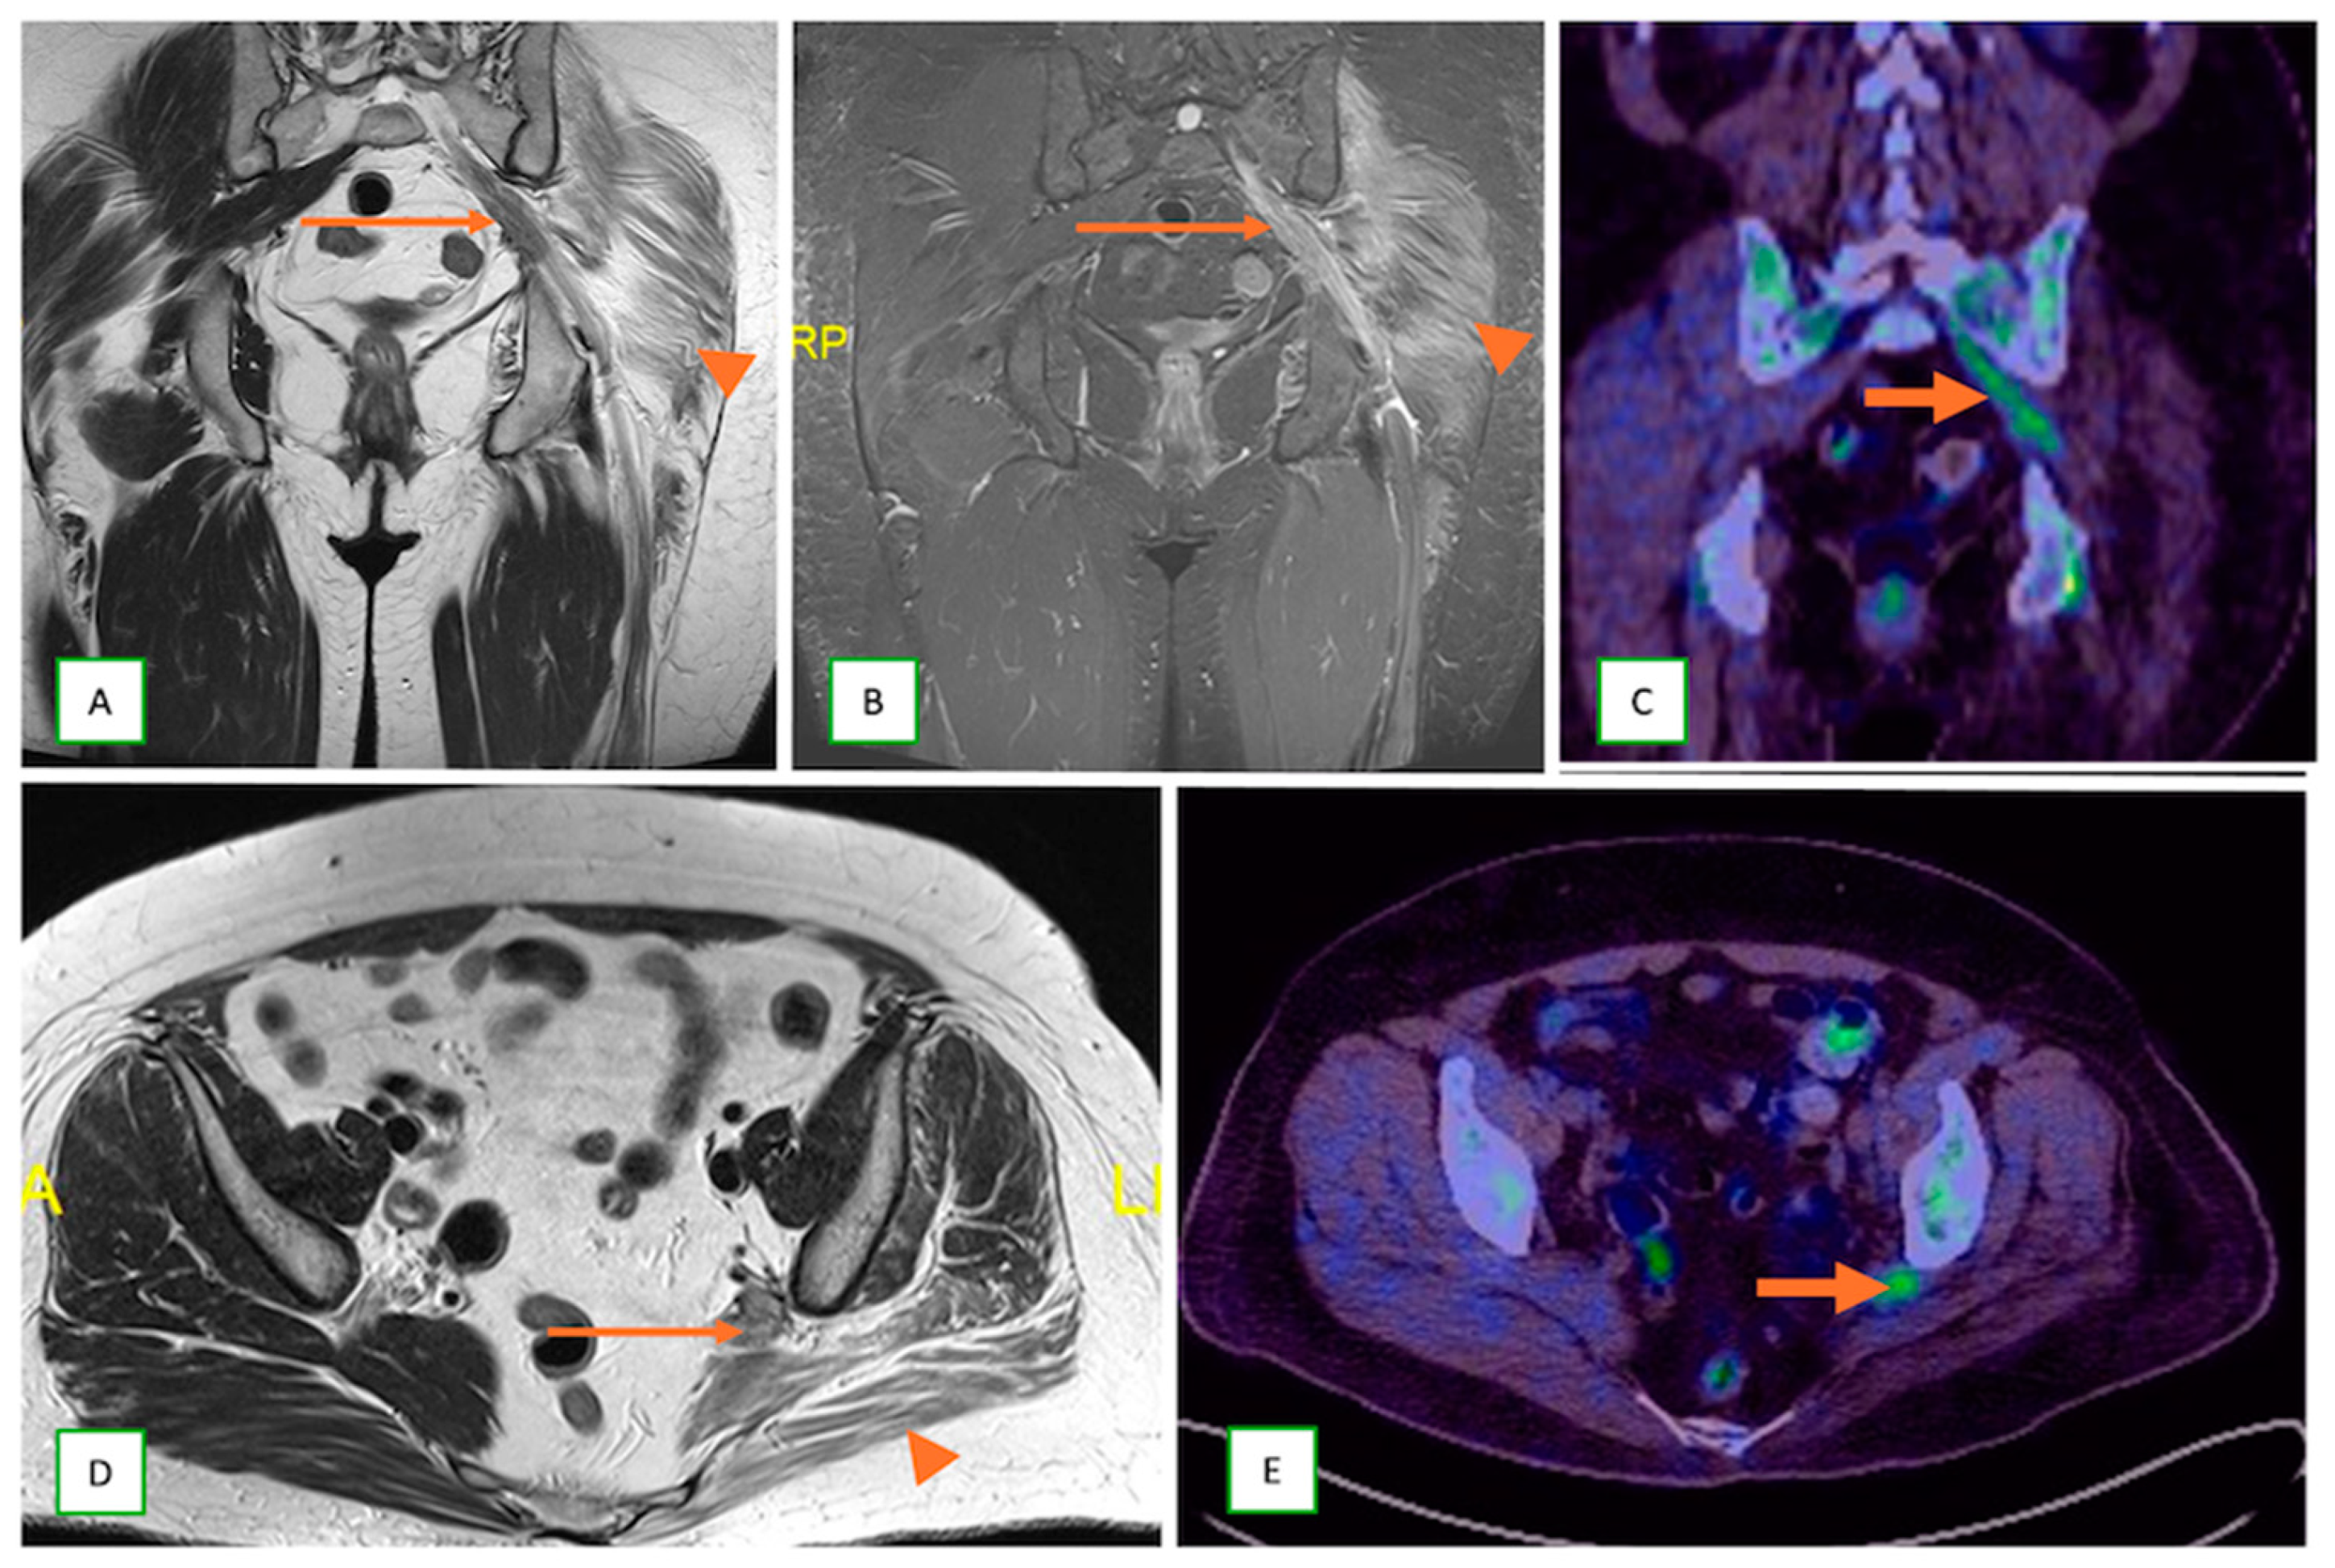

- Neurolymphomatosis describes intraneural spread of lymphoma and appears as diffuse enlargement of nerves, plexuses, spinal cord, and cauda equina. It shows more homogeneous enhancement than PNSTs and may be associated with lymphadenopathy or a known history of lymphoma [63] (Figure 20 and Figure 21).

- Metastatic lesions: These include perineural spread of the tumor or metastasis to peripheral nerves by an adjacent or distant primary tumor. They are commonly observed with head and neck cancers, such as squamous cell carcinoma. They typically appear as linear thickening and enhancement extending along the course of the affected nerve on MRI with end muscle edema and appear FDG-avid on PET-CT [66] (Figure 24 and Figure 25).